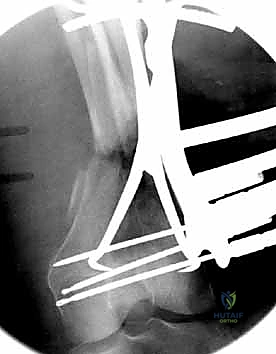

المرحلة الرابعة: التثبيت النهائي بالشرائح والمسامير (Fixation)

يتم استخدام "شرائح الإغلاق التشريحية" (Anatomical Locking Plates) المصنوعة من التيتانيوم عالي الجودة. هذه الشرائح مصممة خصيصاً لتأخذ شكل الجزء السفلي من عظم الفخذ. يتم تمرير الشريحة أسفل العضلات وتثبيتها بمسامير تغلق داخل الشريحة نفسها (Locking Screws)، مما يوفر ثباتاً ميكانيكياً هائلاً، حتى في حالات العظام الهشة.

في بعض الحالات المعقدة جداً، قد يتطلب الأمر استخدام شريحتين (Dual Plating) لضمان عدم تحرك الكسر أثناء فترة التعافي.